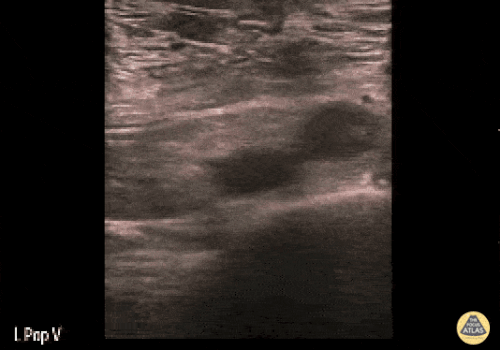

± DVT (Derin Ven Trombozu)

Kalp ve VCI değerlendirmesi sırasında masif pulmoner emboli düşündüren bulgular varsa (RV strain/dilatasyon + pletorik VCI + akciğerlerin temiz görünmesi), bilateral alt ekstremitelerde DVT değerlendirmesi yapılmalıdır.

POCUS ile DVT değerlendirmesinin, yüksek duyarlılık ve özgüllük ile hızlı ve doğru şekilde yapılabildiğini gösteren güçlü kanıtlar vardır.

Femoral ven değerlendirmesi

-

İncelemeye inguinal ligamentin hemen distalinden başlanır.

Ven genellikle arterin medialinde yer alır.

Kompresyon uygulanır; arter hafifçe komprese olana kadar bası sürdürülür.

Eğer ven tamamen kollabe olmuyorsa, inceleme pozitif kabul edilir.

Femoral ven değerlendirilirken, görüntüleme mutlaka:

Greater safen ven ile common femoral ven birleşim noktasının distalini içermelidir.

Femoral vene 5 cm içinde yer alan proksimal safen ven trombüsleri de DVT olarak kabul edilir, bu nedenle safenofemoral bileşke mutlaka görüntülenmelidir.

Ayrıca deep femoral venin common femoral venden ayrıldığı dallanma noktası da değerlendirilmelidir.

Popliteal ven değerlendirmesi

Popliteal damarlar benzer şekilde değerlendirilir:

Popliteal ven, popliteal arterin yüzeyelinde yer alır.

Kompresyon uygulanır.

Anterior ve posterior tibial venler ile fibular (peroneal) ven dallanma noktaları mutlaka kontrol edilmelidir.

Patolojik DVT USG:

| Sol popliteal vende oklüziv DVT

|

Popliteal DVT